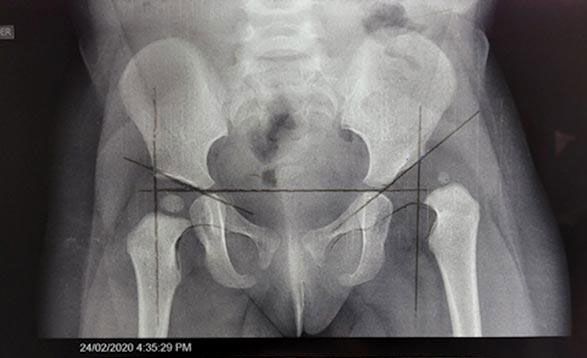

- Luxación Congénita de Cadera: Diagnóstico y corrección de problemas de cadera en recién nacidos.

- Tamiz de cadera

- Displasia de cadera: detección temprana de displasia de cadera por medio de ultrasonido, también conocida como tamiz.